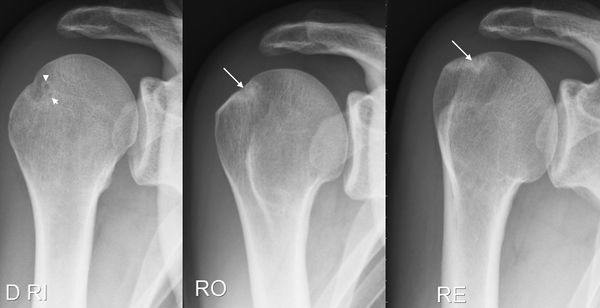

X-ray

Simple radiographic examination is comprised of three views (anteroposterior, Lamy and Bernageau views) Condensation or bone cysts on the greater tubercle and glenoid rim should be investigated for previous posterosuperior impingements (Figure).

Radiological signs found on X-rays.